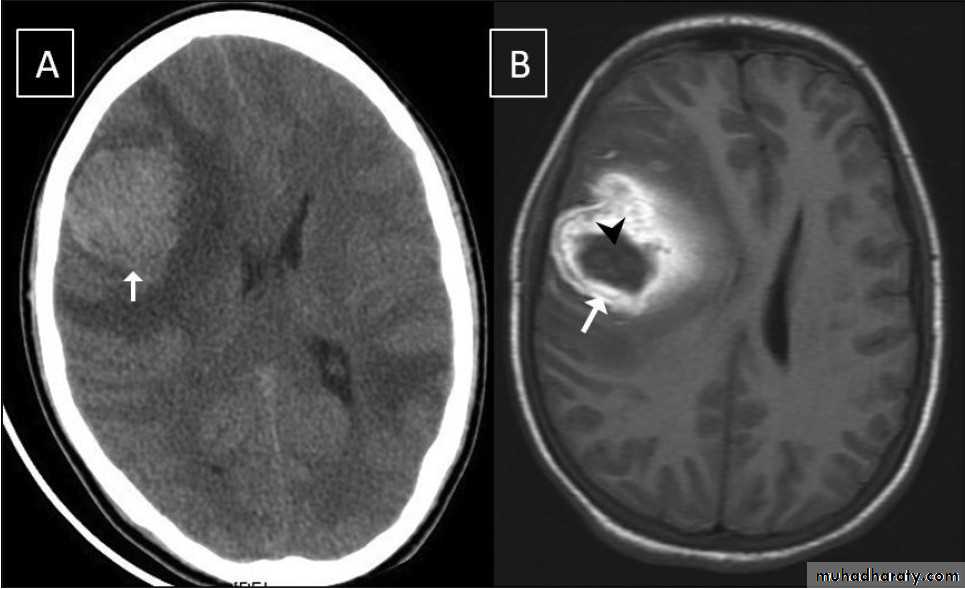

Glioma

Comments primary interracial tumor , vary greatly in malignancy , have many names depending on the histological type :astrocytoma

gliobtastoma multiforme G IV highly malignant t. named also as butterfly G. arise from the anterior or posterior aspect of the corpus callosum , extend & spread to both cerebral hemispheric sides

Low grade G. I well or ill defined lesion iso dence to the brain tissues , not associated with oedeme , no Enhancement , no associated Hemorrhage , necrosis .

From G II , III, various previous finding

IV( glioblastoma multiforme ) are highly malignant have all previous mentioned features .